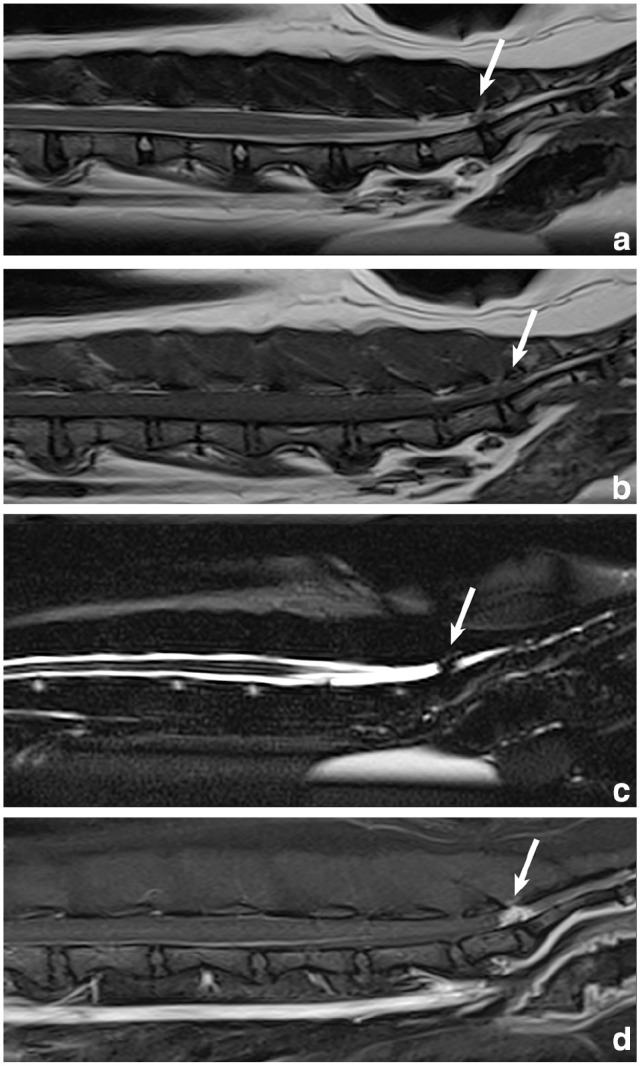

Case summary: A 10-year-old female spayed domestic shorthair cat was evaluated for a 6-week history of abnormal tail carriage and constipation. Examination revealed tail paresis and pain over the lumbosacral and sacrocaudal articulations and on tail manipulation. MRI revealed a contrast-enhancing mass within the vertebral canal over the lumbosacral disc space, compressing the cauda equina. The mass filled the epidural space, resulting in complete attenuation of the cerebrospinal fluid signal. Laminectomy and durotomy were performed over L7-S1, revealing white, firm material within the subarachnoid space. Microscopically, the material was consistent with degenerative intervertebral disc material. Postoperatively, the clinical signs resolved completely.

Relevance and novel information: Intervertebral disc herniation (IVDH) is uncommon in cats, with most cases involving extradural compression of nervous tissue. Reports describing intramedullary intervertebral disc extrusions in cats are rare. To the authors' knowledge, the present case is the first reported intradural-extramedullary intervertebral disc extrusion in a cat. Although MRI can often delineate extradural lesions, it can be insensitive in differentiating intradural-extramedullary from intramedullary lesions. In the present case, the location of the lesion within the vertebral canal at the lumbosacral disc space made the determination of the lesion's location with respect to the meninges challenging. Moreover, the strong contrast enhancement of the lesion raised an index of suspicion for neoplasia. Surgical intervention and histopathology confirmed an intradural-extramedullary IVDH. The present case adds to a growing body of literature regarding IVDH in cats and details the imaging findings of intradural-extramedullary IVDH in a cat.